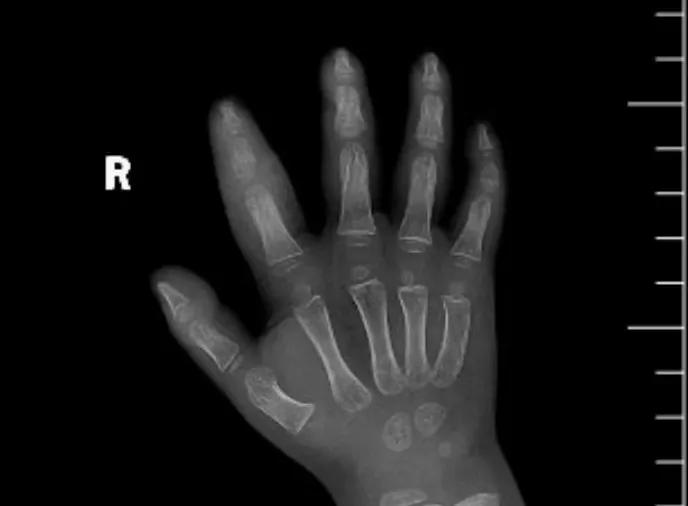

近日,市二院顯微外科接診一名3歲半的小患者,被玉米葉割傷右食指,因家長疏忽大意,導(dǎo)致一個(gè)小小的傷口竟然發(fā)展成了骨髓炎。來院時(shí)患兒右食指腫脹明顯,既不能伸也不能彎,皮膚發(fā)燙,疼得哇哇大哭。

第三天開始,月月哭鬧不止,一直說手疼,怎么哄也不行,于是在當(dāng)?shù)蒯t(yī)院治療了10來天,然而月月的手指依然腫得像個(gè)胡蘿卜,疼痛感依然存在。此時(shí),月月的媽媽才覺得事情不大對(duì)勁,于是經(jīng)過打聽,慕名來到市二院顯微外科。入院后,經(jīng)檢查發(fā)現(xiàn),月月的右食指骨質(zhì)有侵蝕,骨骺有缺損,甚至?xí)绊懸院笫种傅陌l(fā)育。聽到這個(gè)消息,月月媽媽感覺心都揪住了。